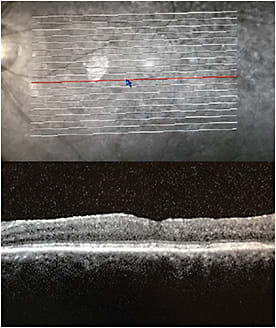

By the time the patient returned for her July 8, 2015 follow-up visit, 3 months after the second dexamethasone intravitreal implant OS, the effects of the implant were waning. Central subfield thickness (CST) as measured by OCT had increased to 281 µm and visual acuity (VA) had declined to 20/50+2 (Figure 1). At the next visit, Aug. 26, 2015, CST and VA further worsened to 392 µm and 20/60 and Iluvien was implanted (Figure 2).

At the patient’s first follow-up visit, 1 week after Iluvien implantation OS, Sept. 2, 2015, the retinal anatomy had normalized and VA improved to 20/40-1 (Figure 3). With the patient still using three IOP-lowering medications, intraocular pressure remained unchanged since before the implant at 14 mmHg. IOP remained stable at the next visit on Oct. 28, 2015, and VA further improved to 20/30+1 (Figure 4). While I’d typically recommend that this patient see me every 3 months, she also sees a glaucoma specialist. We’ve scheduled the visits so that she sees each of us every 6 months, but she’s examined every 3 months. I continue to measure IOP at every visit. Today, more than a year after Iluvien was placed in the left eye, the patient’s vision is consistently better than it had been in more than a decade, and we’re both thrilled that she’s been able to carry on with her busy real estate business on a much easier office visit schedule than she had been enduring.